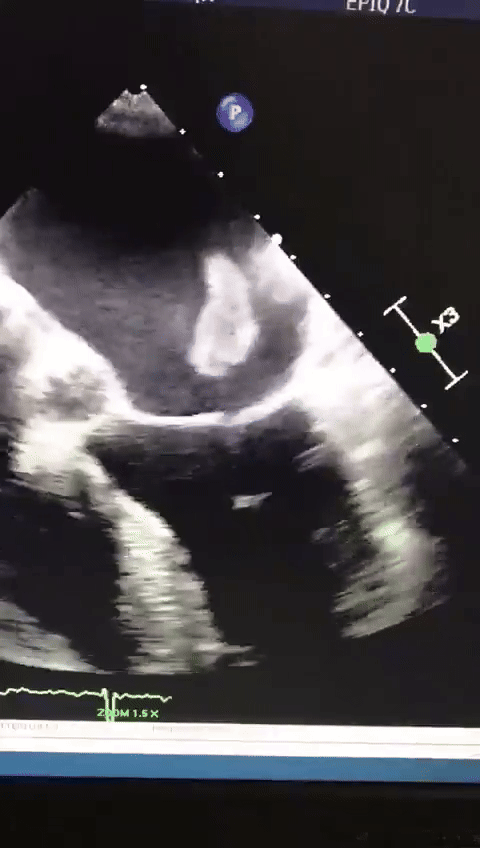

[흥미돋]심장 판막에서 뛰고있는 혈전